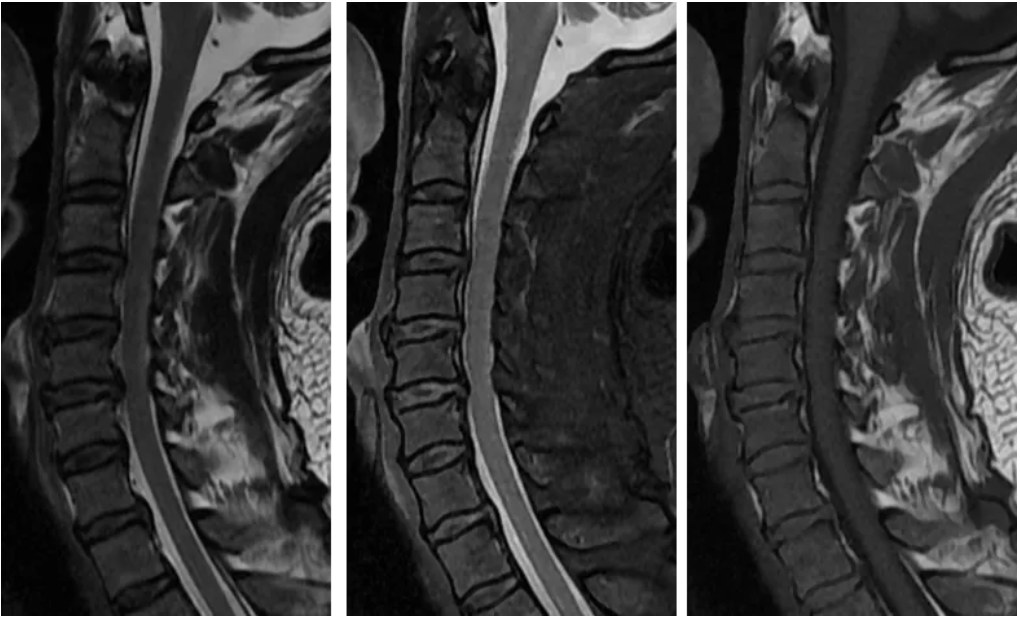

段金辉 新乡医学院第一附属医院 一、病史 男性,54岁,双上肢麻木,下肢无力 临床申请:颈椎MRI平扫检查 一看就知道,颈椎病。 天天做。 这个好简单。 心情好的时候,仨Sag一Ax。俩sag一Ax也能解决问题。 二、开始干活 Sag T2 / T2 Flex / T1 FSE 序列分别如下所示:

很简单。 椎间盘突出。 想看清椎间盘突出,最好用的序列莫过于横断面梯度回波序列T2*WI MERGE(multiecho recalled gradient echo,多回波的梯度回波序列)。与常规T2WI FSE序列相比,其优点在于脑脊液流空伪影很少。所以,脑脊液呈显著高信号,突出的椎间盘呈低信号,二者之间对比差异很大,图像效果杠杠滴。